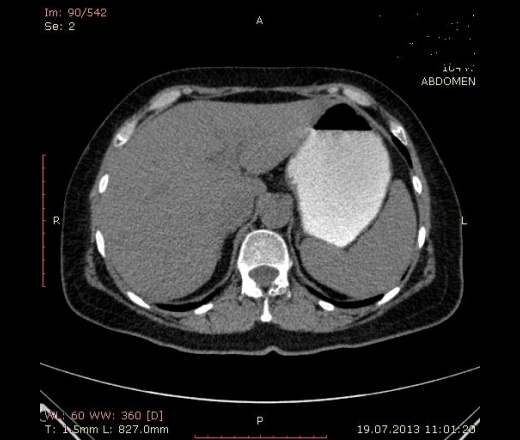

Банально, но надо контрастировать. Еще лучше сделать МРТ. По нативу согласна с результатом УЗИ: сладж?образование? Возможно, такой шикарный камень, либо заброс контраста из 12 перстной кишки, хотя в холедохе и внутрипеченочных путях его вроде не видно.

К сожелению данных УЗИ у меня нет.Холедох , внутипеченочные протоки не расширены, но пузырнвй проток расширен , извитой имеет плотность 36-38 ед.Н. Завтра утром беру на в\в контрастирование, но хирурги к12 часям хотят брать на операцию.Мне нужно предварительно написать заключение.Если опухоль ж.пузыря какая картина должно быть после в\в контрастирование, подскажите.Если у вас есть свое наблюдение выложите на сайт .Пожалуйста.